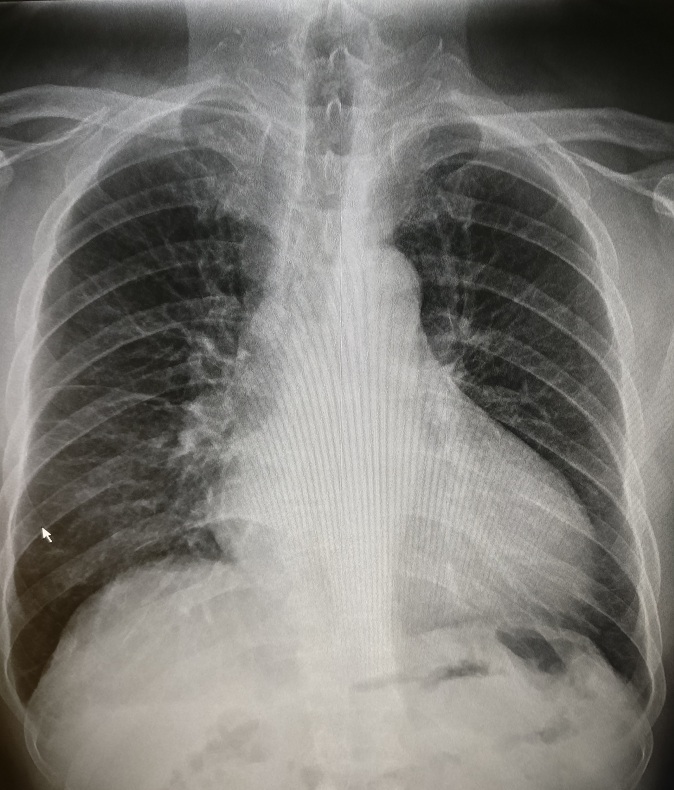

4.右心房增大

主要见于右心衰竭、先心病如房间隔缺损、三尖瓣病变等。见图4。

图4 房间隔缺损,以右房增大为主,右肺动脉干增宽,肺动脉段明显膨隆

5.肺循环高压

分为肺动脉高压及肺静脉高压。

(1)肺动脉高压:肺动脉收缩压大于30 mmHg或平均动脉压大于20 mmHg,可由肺充血或是肺循环阻力增加(如肺内小血管狭窄或痉挛等)引起。可见图4。